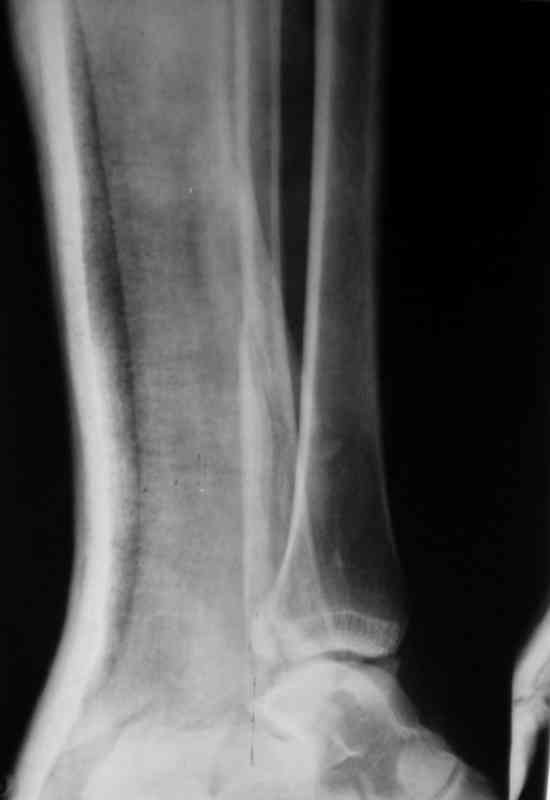

Пациентка, 30 лет с таким переломом. Произвел репозицию.

Теперь думаем, то ли так оставить, или все-таки, выполнить остеосинтез согласно рекомендациям АО? Хотелось бы услышать мнение коллег -- С ув. Sergey Melashenko